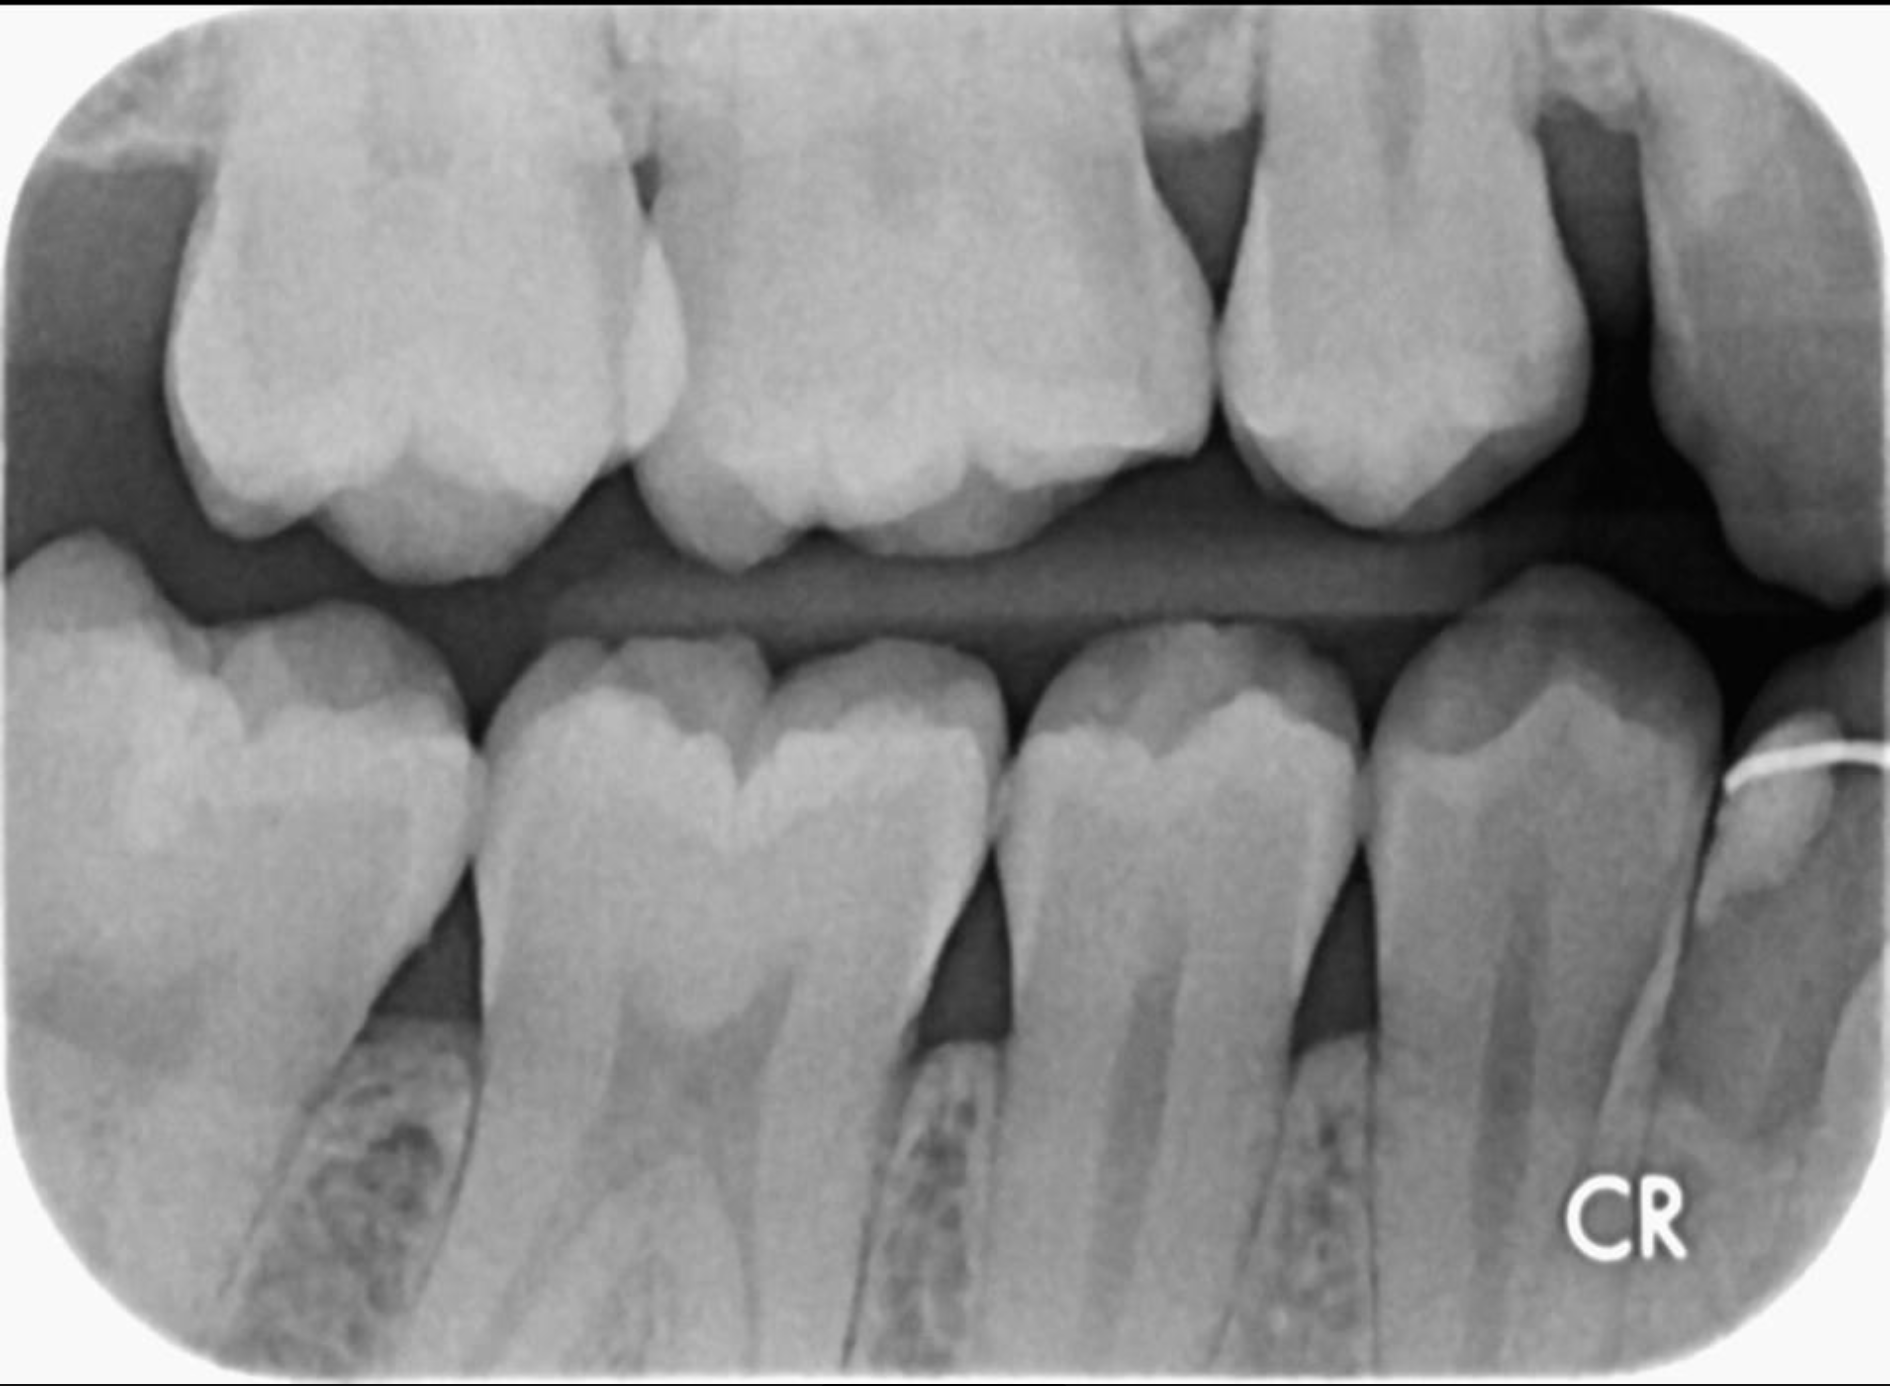

Ik ben 3 jaar niet naar de tandarts geweest ivm verhuizing naar een andere stad. Nu ben ik gisteren bij mijn nieuwe tandarts geweest en die heeft een controle gedaan en geconstanteerd dat ik een (beginnend) gaatje heb. Ik heb de rontgenfoto's opgevraagd achteraf, maar zie niet precies waar dat gaatje zou moeten zitten. Kan iemand mij hierbij helpen? Ik heb nog nooit een gaatje gehad, dus wil zeker weten of deze tandarts wel gelijk heeft voordat hij mijn mond gaat bewerken.

ik zie in ieder geval in de 36 distaal iets, maar ik zie op meer plekken iets (36 wel de duidelijkste en zo te zien wel een die echt behandeld moet) .